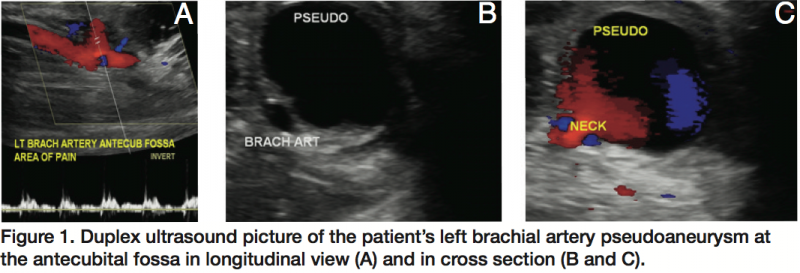

A 17-year-old male patient presented to us as a transfer from an outside hospital with a history of swelling, bruising, and pain in his left antecubital fossa. He had donated blood at his high school 10 days prior to this presentation, where only one needle stick was used to draw his blood. In the emergency room at the outside hospital, an ultrasound of the affected area was performed and it showed a 2.3 cm mass with turbulent arterial flow, diagnosed as a left brachial artery pseudoaneurysm. His parents requested transfer to a tertiary care center for definitive repair. On our initial exam, the patient complained of pain in that arm, but had no motor or sensory deficits. The left radial pulse was readily palpable and the left ulnar pulse had a strong Doppler signal. There was a palpable pulsatile mass in his left antecubital fossa with overlying ecchymosis. Of note, the patient’s medical history was negative except for tonsillectomy and an allergy to aspirin. His coagulation studies were normal.